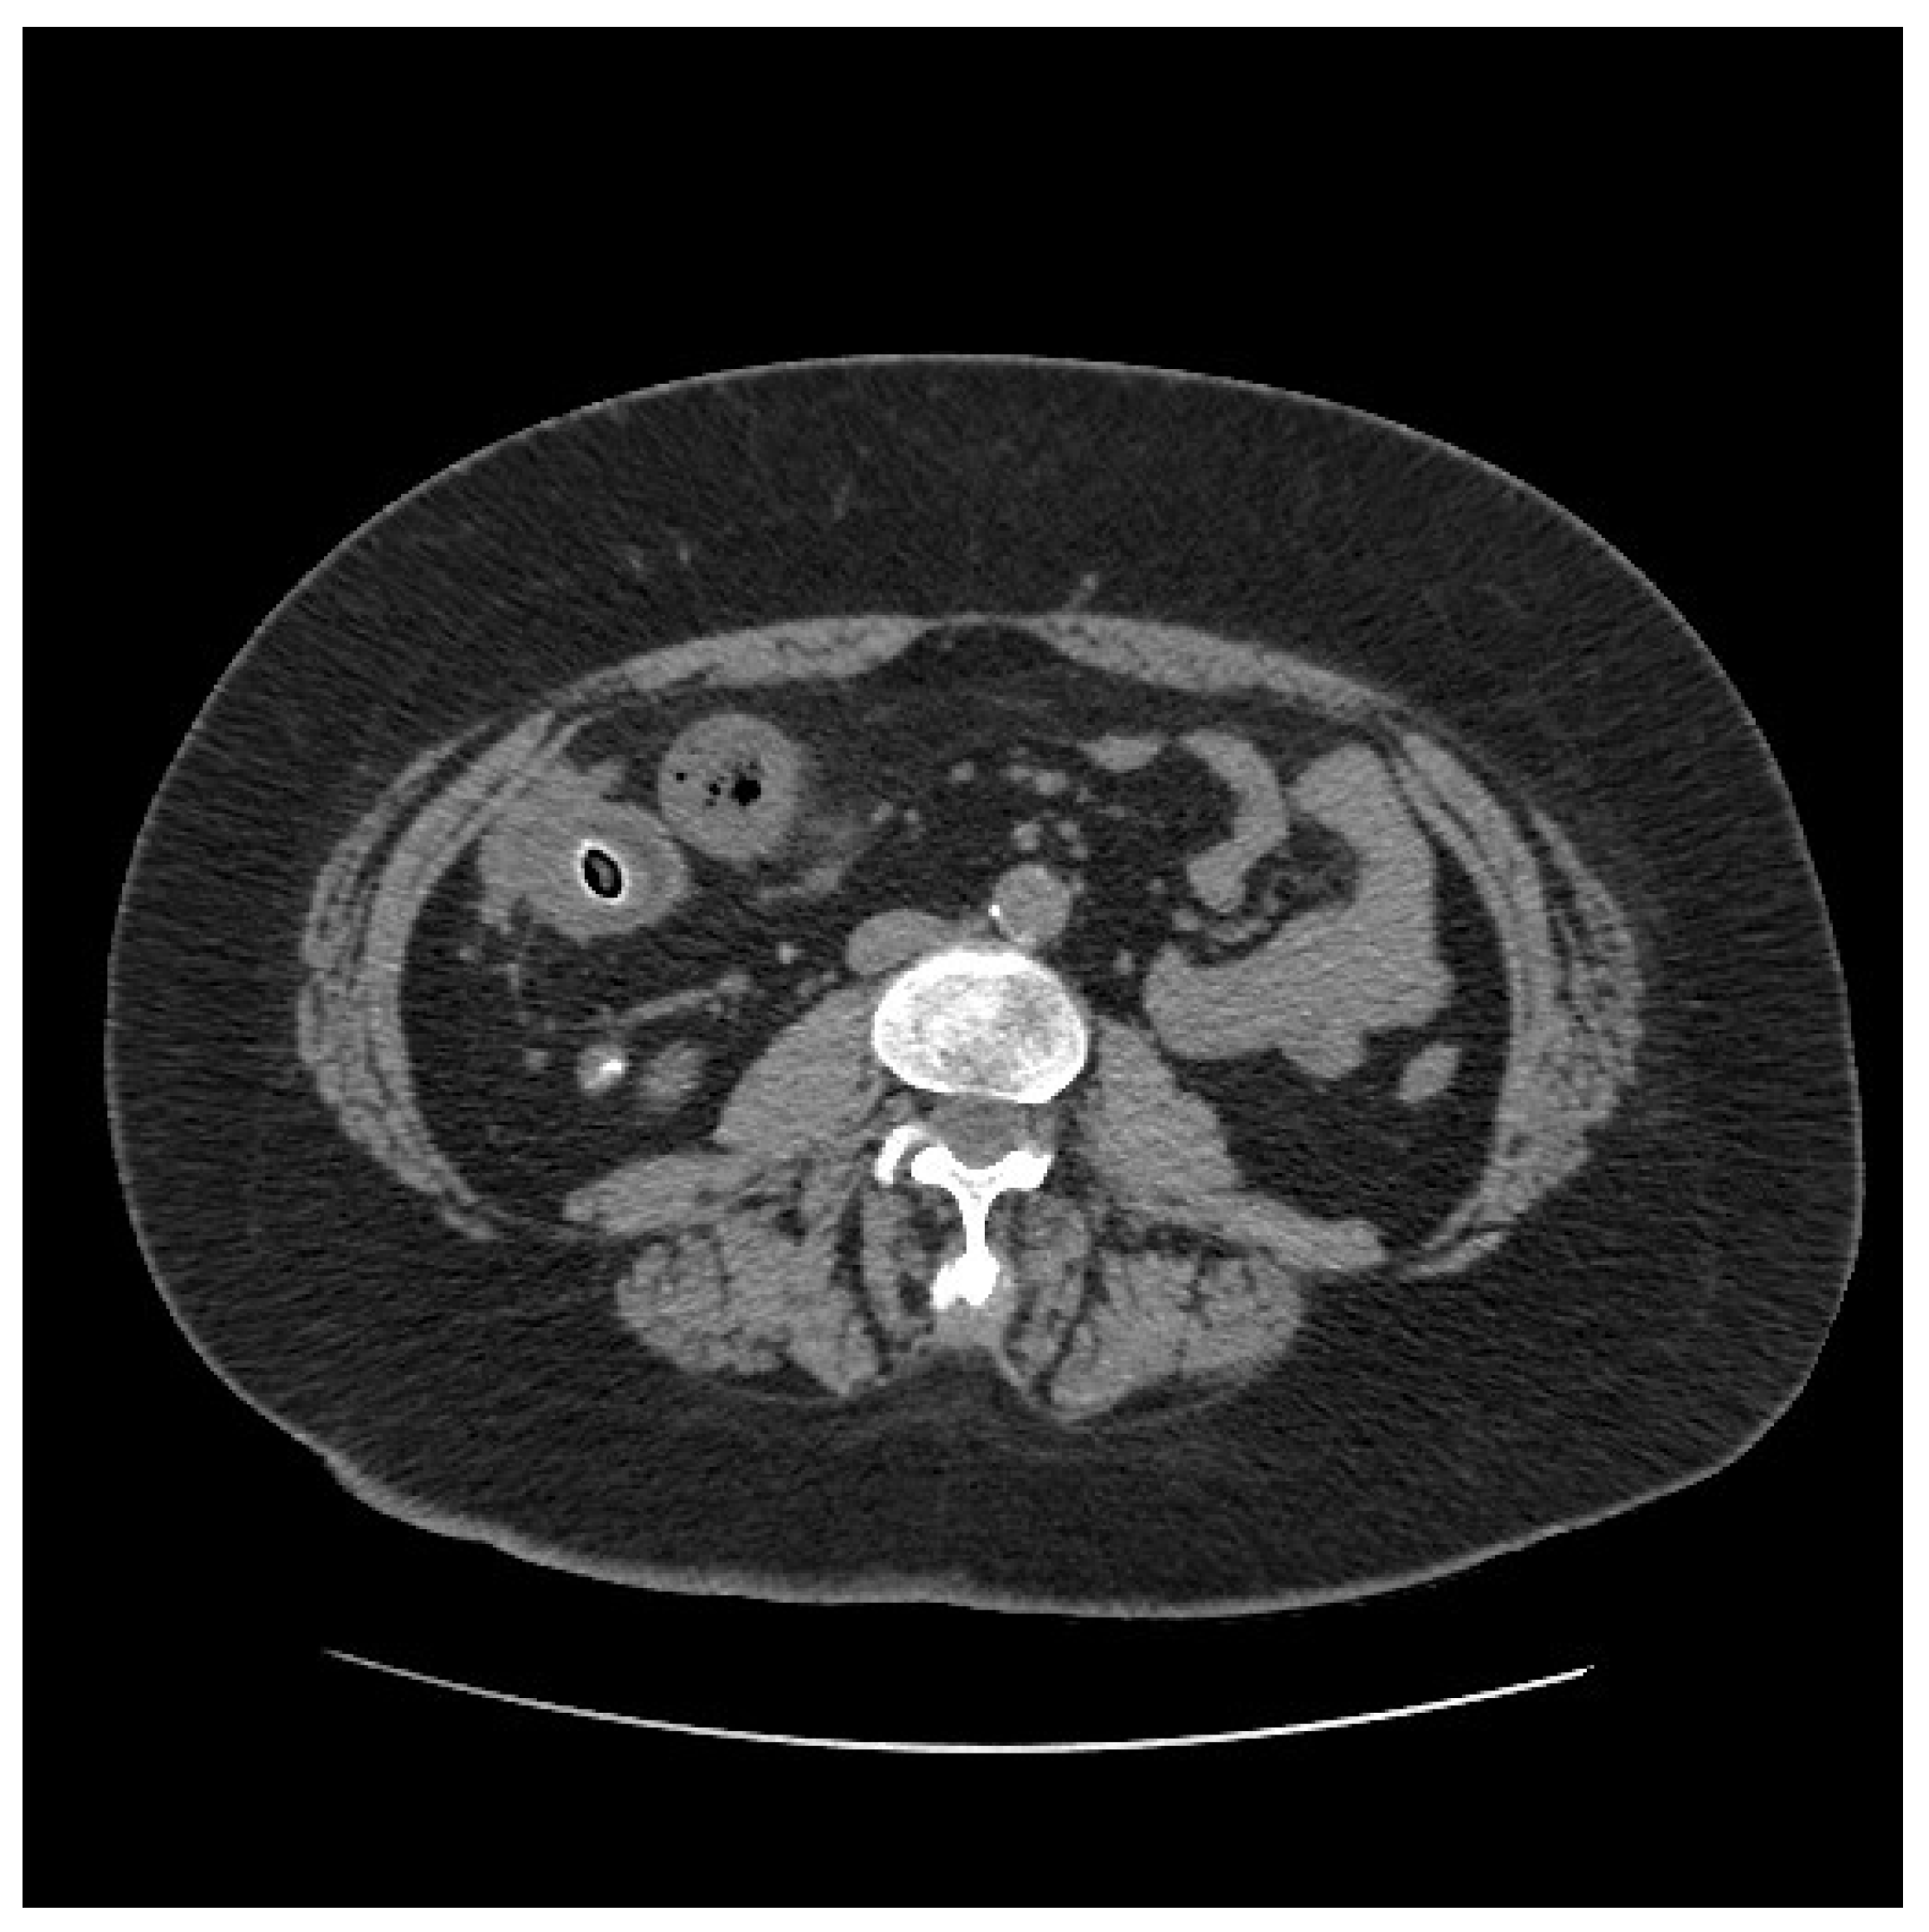

Figure 3.

Computed tomography scan showing small bowel thickening with a 12 mm intraluminal radiopaque mass.

On clinical examination, the abdomen was tender all over the quadrants with absence of peritoneal signs. Laboratory tests showed an increased white blood cell count of 14,000/mm3 and a C-reactive protein of 26.2 mg/dl. Computed tomography scan showed small bowel thickening with a 12 mm intraluminal radiopaque mass (Figure 3). Colonoscopy showed an inflammatory (ulcerated) but serrated stenosis of the terminal ileum with patency of ileocecal valve, suspicious for ileal CD (Figure 4). Magnetic resonance imaging showed thickening of the distal ileum, 7 cm in length, without the presence of the fruit pit, that had been physiologically expelled from the colon (Figure 5). Due to the nature of the stenosis, which was inflammatory, a “wait and see approach” was chosen. After a brief course of systemic prednisone, which failed to obtain any clinical benefit, ileocecal resectionwas performed with resolution of all symptoms.